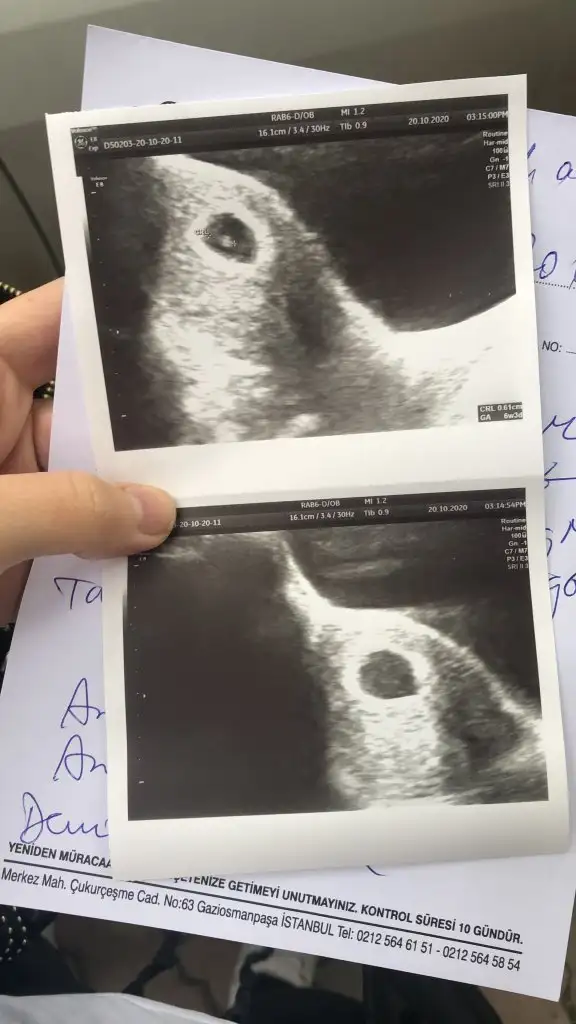

Ya ben hiç anlamam bu işlerden ama kayınvalidem şıp diye biliyor ya da sallıyor ilkinde baktı keseye erkek bu kesin dedi tuttu şimdi de baktırdık kız bunlar kesin dedi bakacağız bakalımMerhaba kızlar ben suan 6+3 gunluk hamıleyim 3 gun once tam 6 haftalıkken keseyi gorduk ve kalp atısını dinlettı doktorYa aslında bu cok onemsiz bi detay ama insan yinede merak edıyor kese şekline gore cinsiyet tahmını yapılıyormus aranızda anlayan var mı bakınca ne hissediyorsunuz

Bende anlamam böyle kese şeklinden ama bakınca erkek diye hissettimMerhaba kızlar ben suan 6+3 gunluk hamıleyim 3 gun once tam 6 haftalıkken keseyi gorduk ve kalp atısını dinlettı doktorYa aslında bu cok onemsiz bi detay ama insan yinede merak edıyor kese şekline gore cinsiyet tahmını yapılıyormus aranızda anlayan var mı bakınca ne hissediyorsunuz

Kız kesesi gibi duruyorMerhaba kızlar ben suan 6+3 gunluk hamıleyim 3 gun once tam 6 haftalıkken keseyi gorduk ve kalp atısını dinlettı doktorYa aslında bu cok onemsiz bi detay ama insan yinede merak edıyor kese şekline gore cinsiyet tahmını yapılıyormus aranızda anlayan var mı bakınca ne hissediyorsunuz

Bence kese ile cinsiyetin alakası yok benim kızımda kese fasulye gibi Di ince uzunMerhaba kızlar ben suan 6+3 gunluk hamıleyim 3 gun once tam 6 haftalıkken keseyi gorduk ve kalp atısını dinlettı doktorYa aslında bu cok onemsiz bi detay ama insan yinede merak edıyor kese şekline gore cinsiyet tahmını yapılıyormus aranızda anlayan var mı bakınca ne hissediyorsunuz